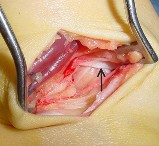

Question 3:

A 22-year-old soccer player sustains a twisting injury to his knee during a match. Radiographs reveal a small elliptical bone fragment adjacent to the lateral tibial plateau (Segond fracture). Based on this radiographic finding, which physical exam maneuver is most likely to be positive in this patient?

A Segond fracture is an avulsion fracture of the anterolateral ligament (ALL) and lateral capsule from the lateral tibial plateau. It is highly pathognomonic (up to 75-100% predictive value) for an anterior cruciate ligament (ACL) tear. The pivot shift test is the most specific physical examination finding for assessing rotational laxity associated with an ACL-deficient knee.